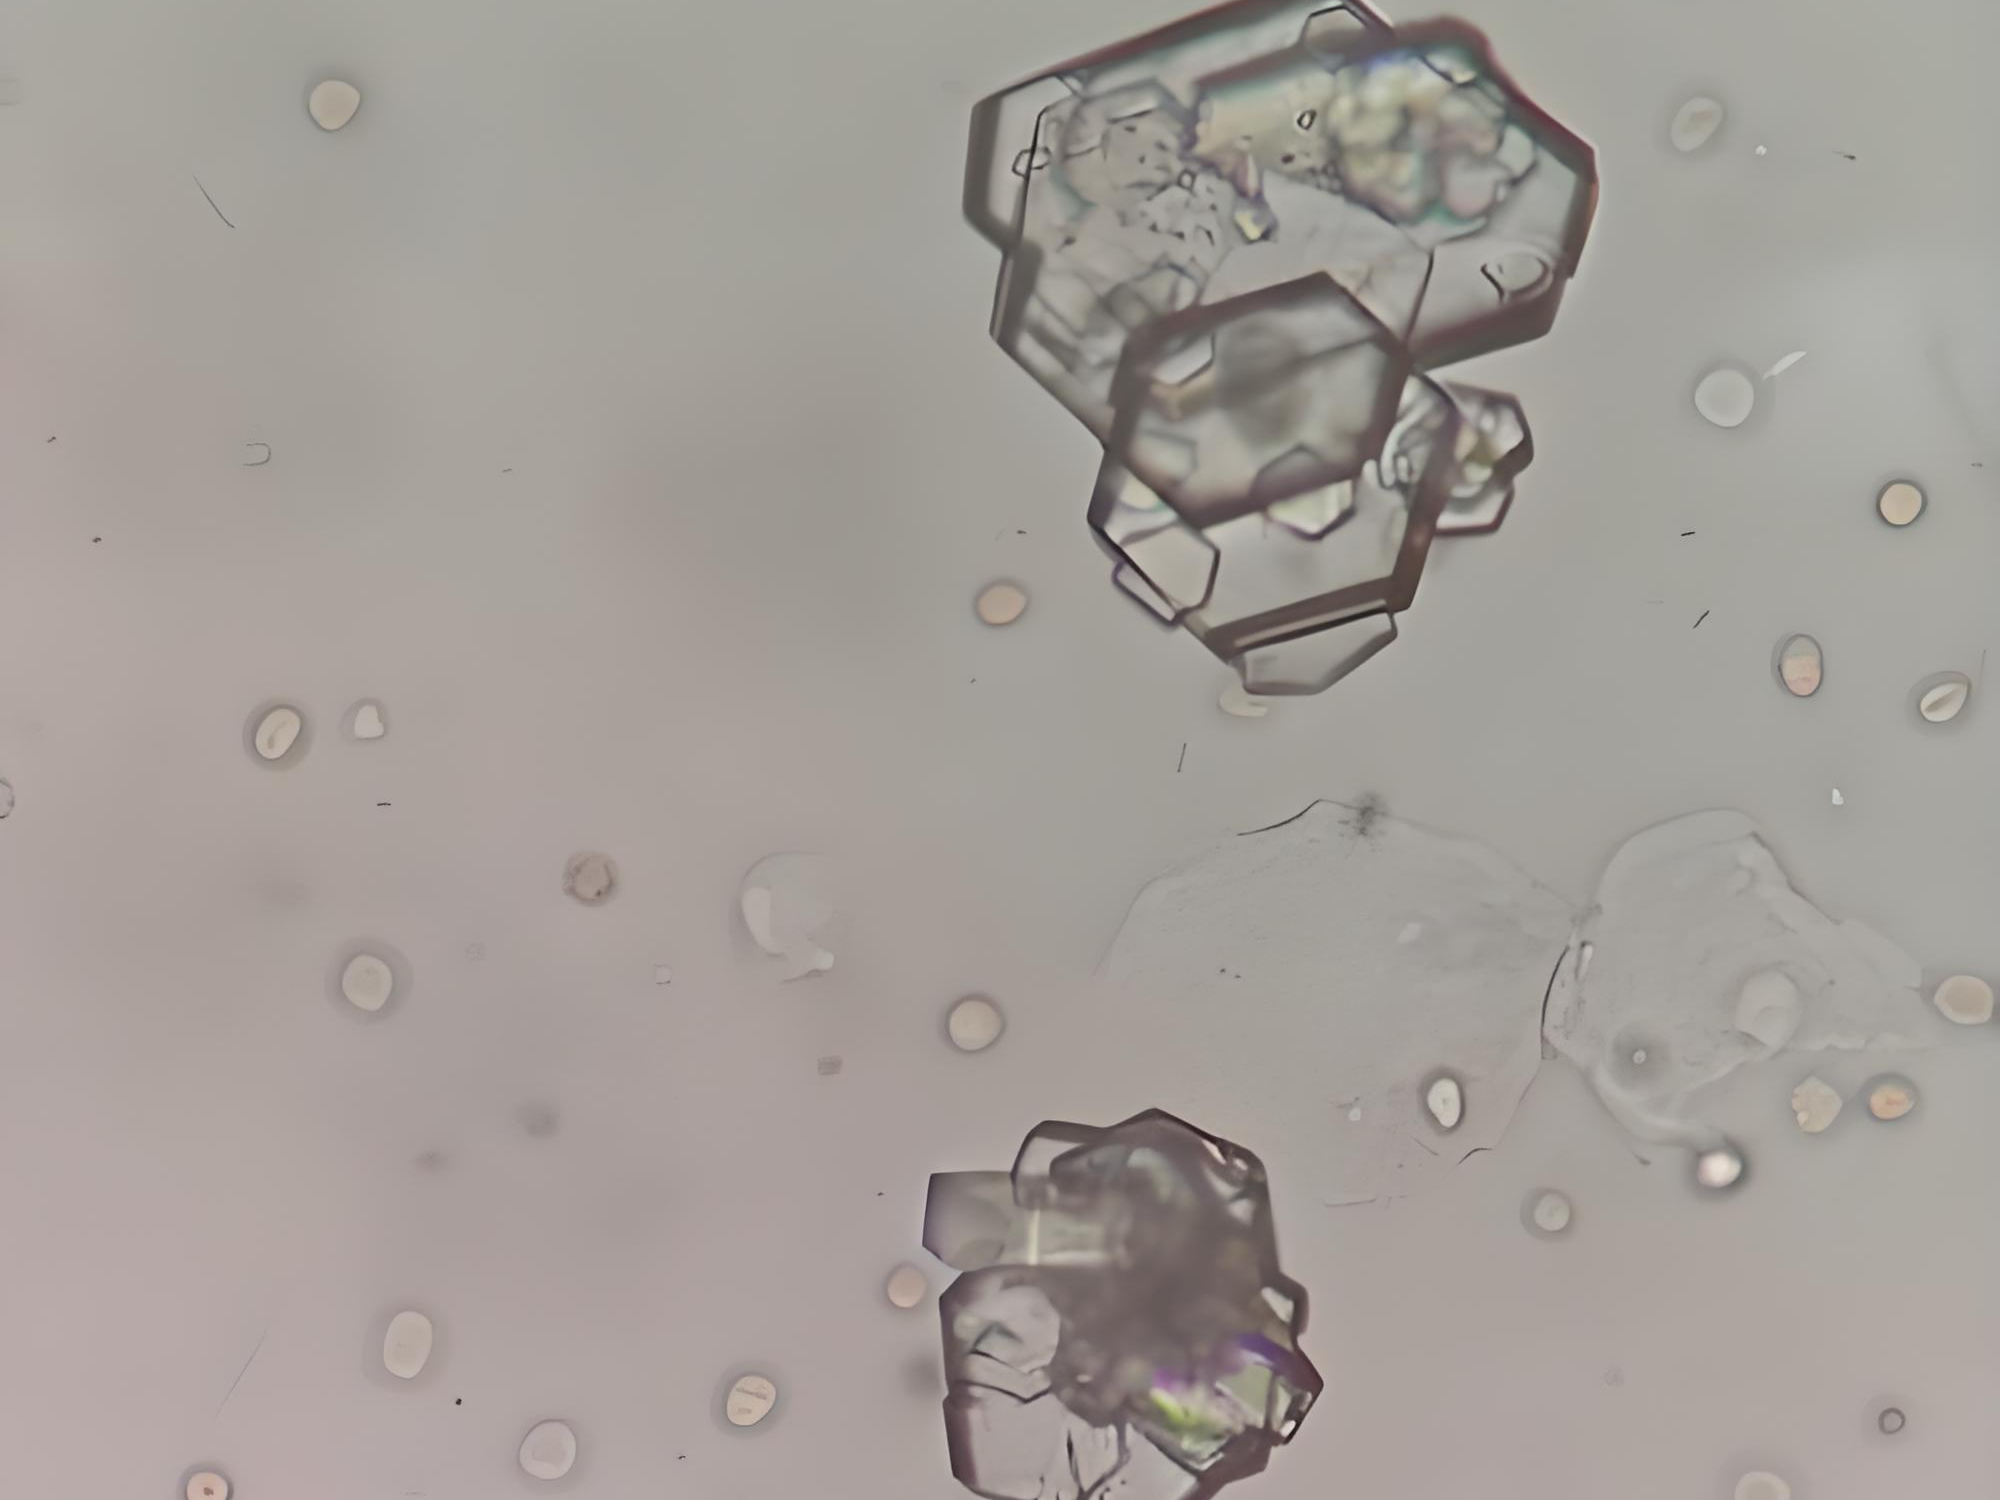

外观:颜色通常较浅,可呈淡黄色,纯胱氨酸成分。显微镜下最具特征的是六边形片状晶体,这种规整的几何形态在偏振光显微镜下尤为明显。